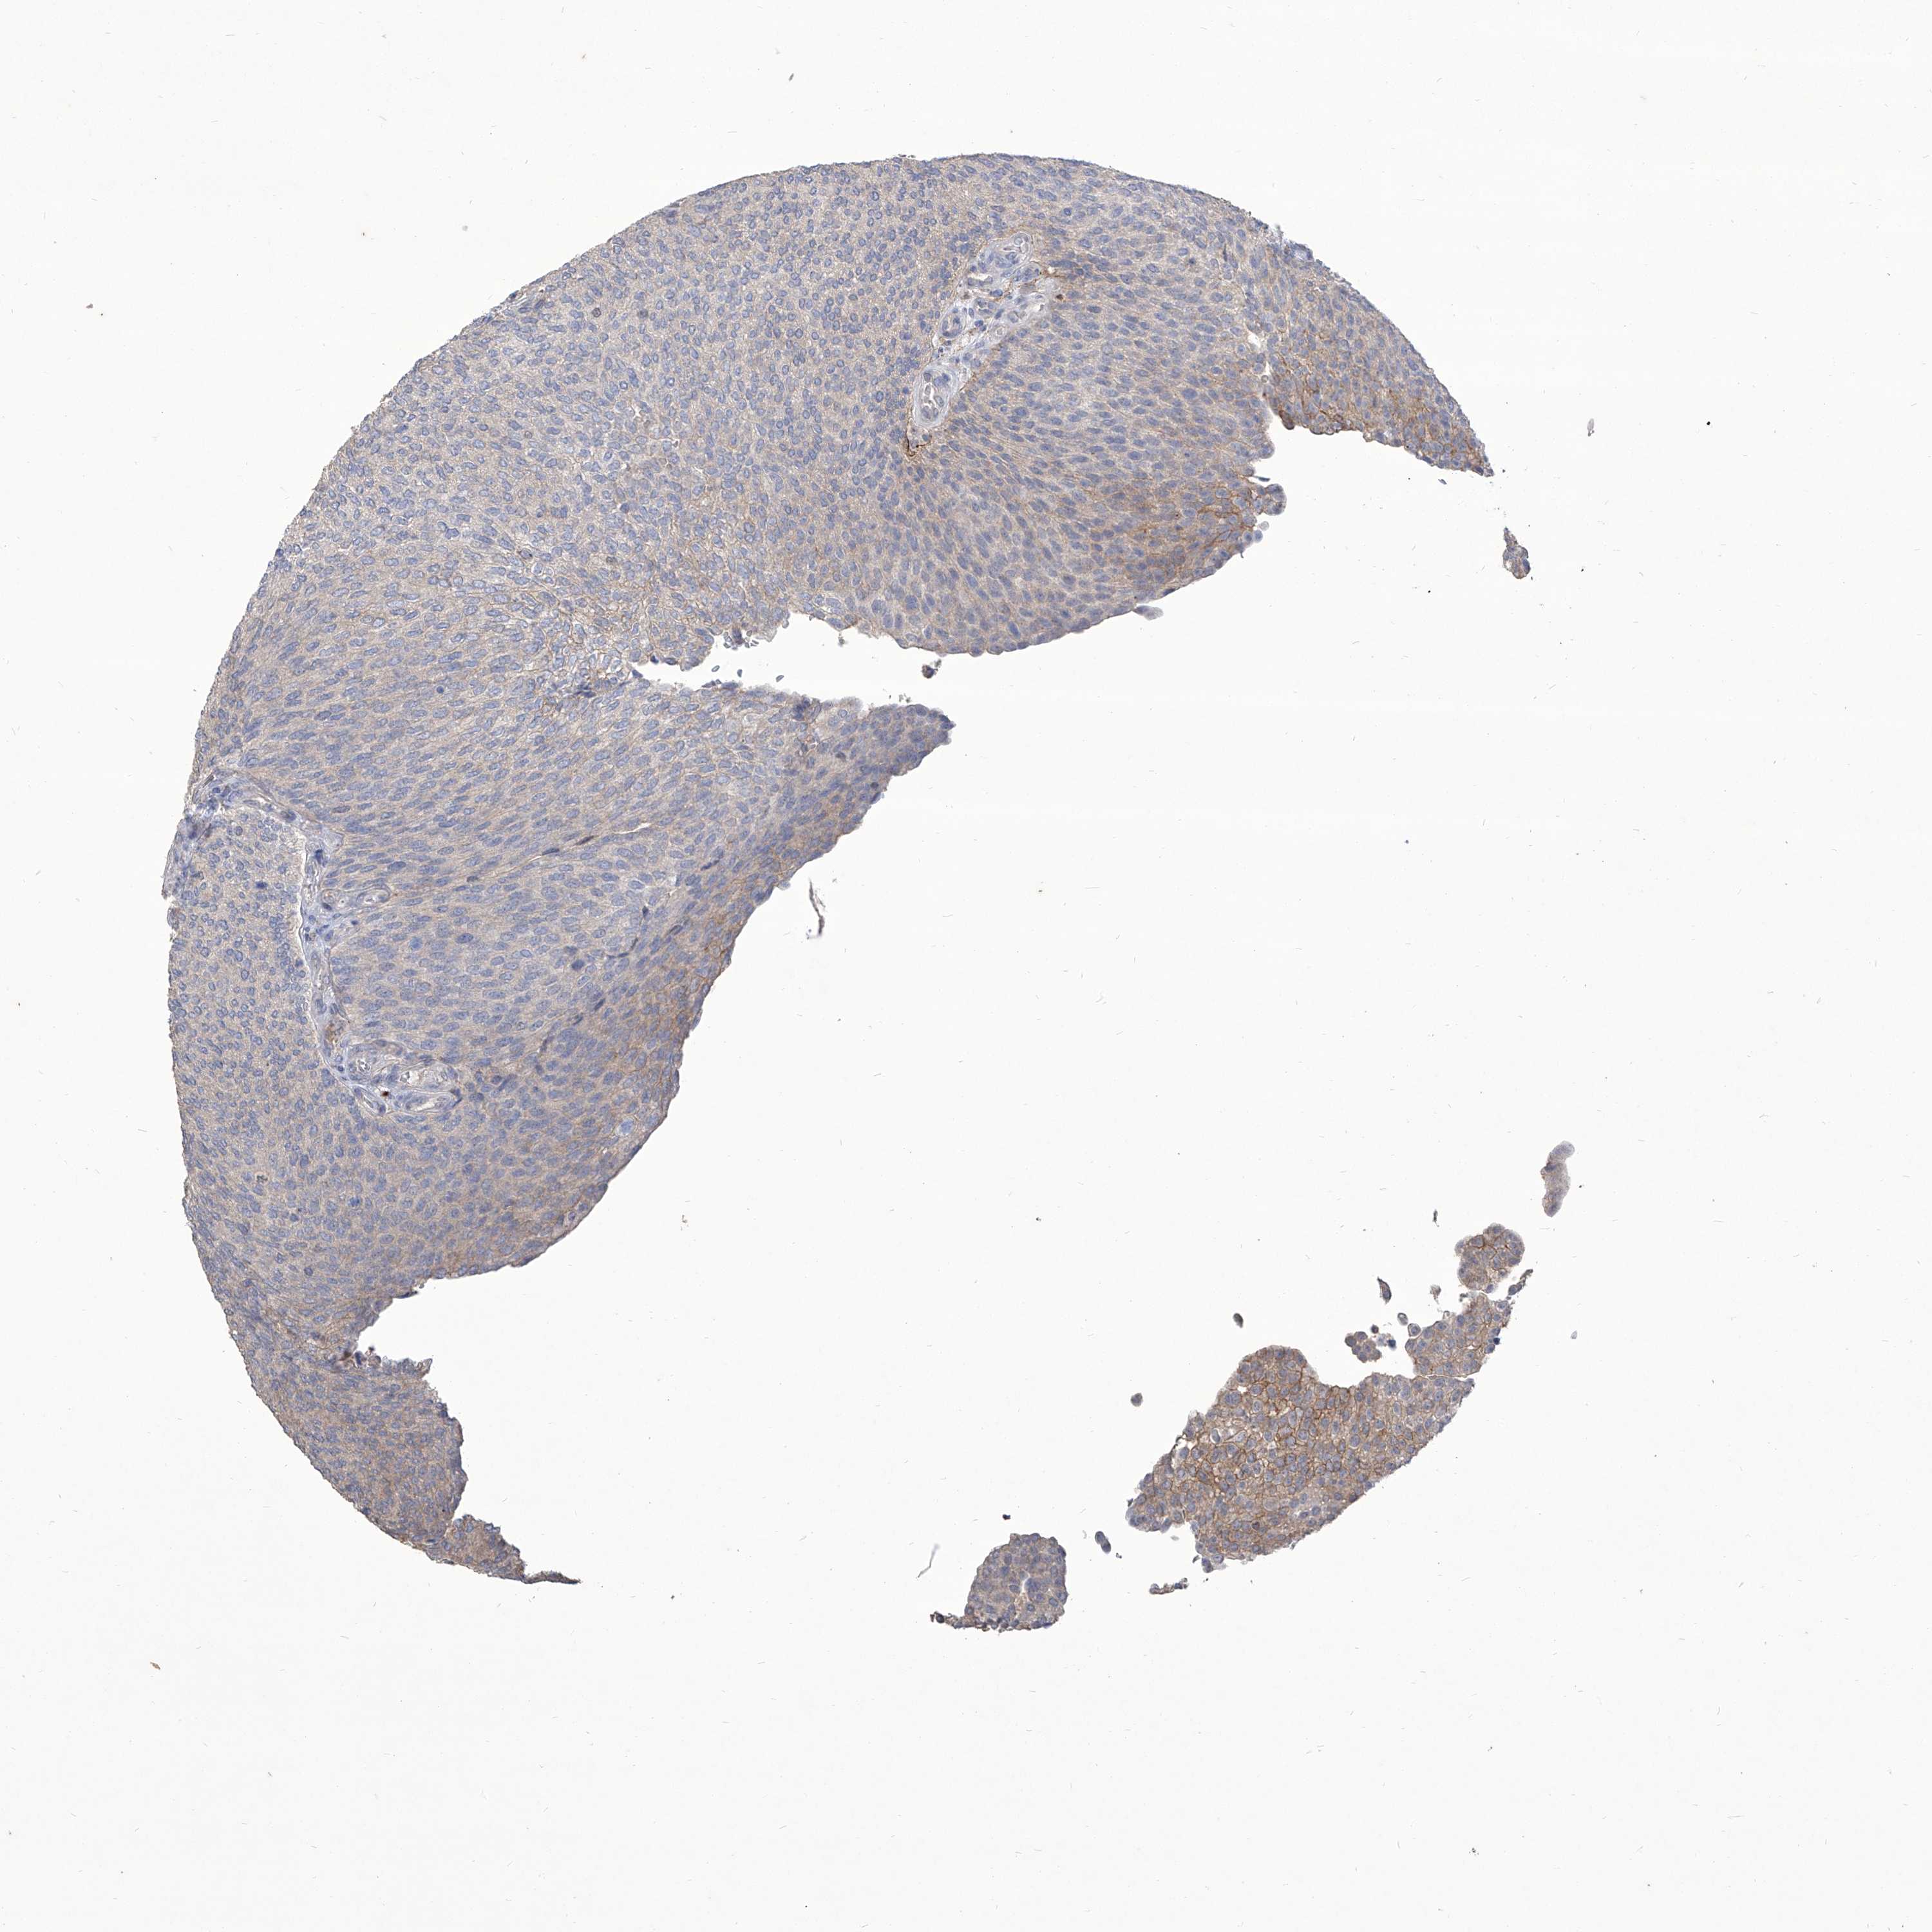

UROTHELIAL CANCER - Protein expressioni

A mouse-over function shows sample information and annotation data. Click on an image to view it in a full screen mode. Samples can be filtered based on level of antibody staining by selecting one or several of the following categories: high, medium, low and not detected. The assay and annotation is described here.

Note that samples used for immunohistochemistry by the Human Protein Atlas do not correspond to samples in the TCGA dataset.

Antibody stainingi

Antibody staining in the annotated cell types in the current human tissue is reported as not detected, low, medium, or high, based on conventional immunohistochemistry profiling in selected tissues. This score is based on the combination of the staining intensity and fraction of stained cells.

Each image is clickable and will lead to virtual microscopy that enables deeper exploration of all samples and also displays staining intensity scores, fraction scores and subcellular localization as well as patient and tissue information for each sample.

Antibody HPA031085

Antibody HPA053694

Staining

High

Medium

Low

Not detected

Intensity

Strong

Moderate

Weak

Negative

Quantity

>75%

75%-25%

<25%

None

Location

Nuclear

Cytoplasmic/membranous

Cytoplasmic/membranous,nuclear

Urothelial carcinoma, Low grade

Urothelial carcinoma, High grade

Urothelial carcinoma, NOS